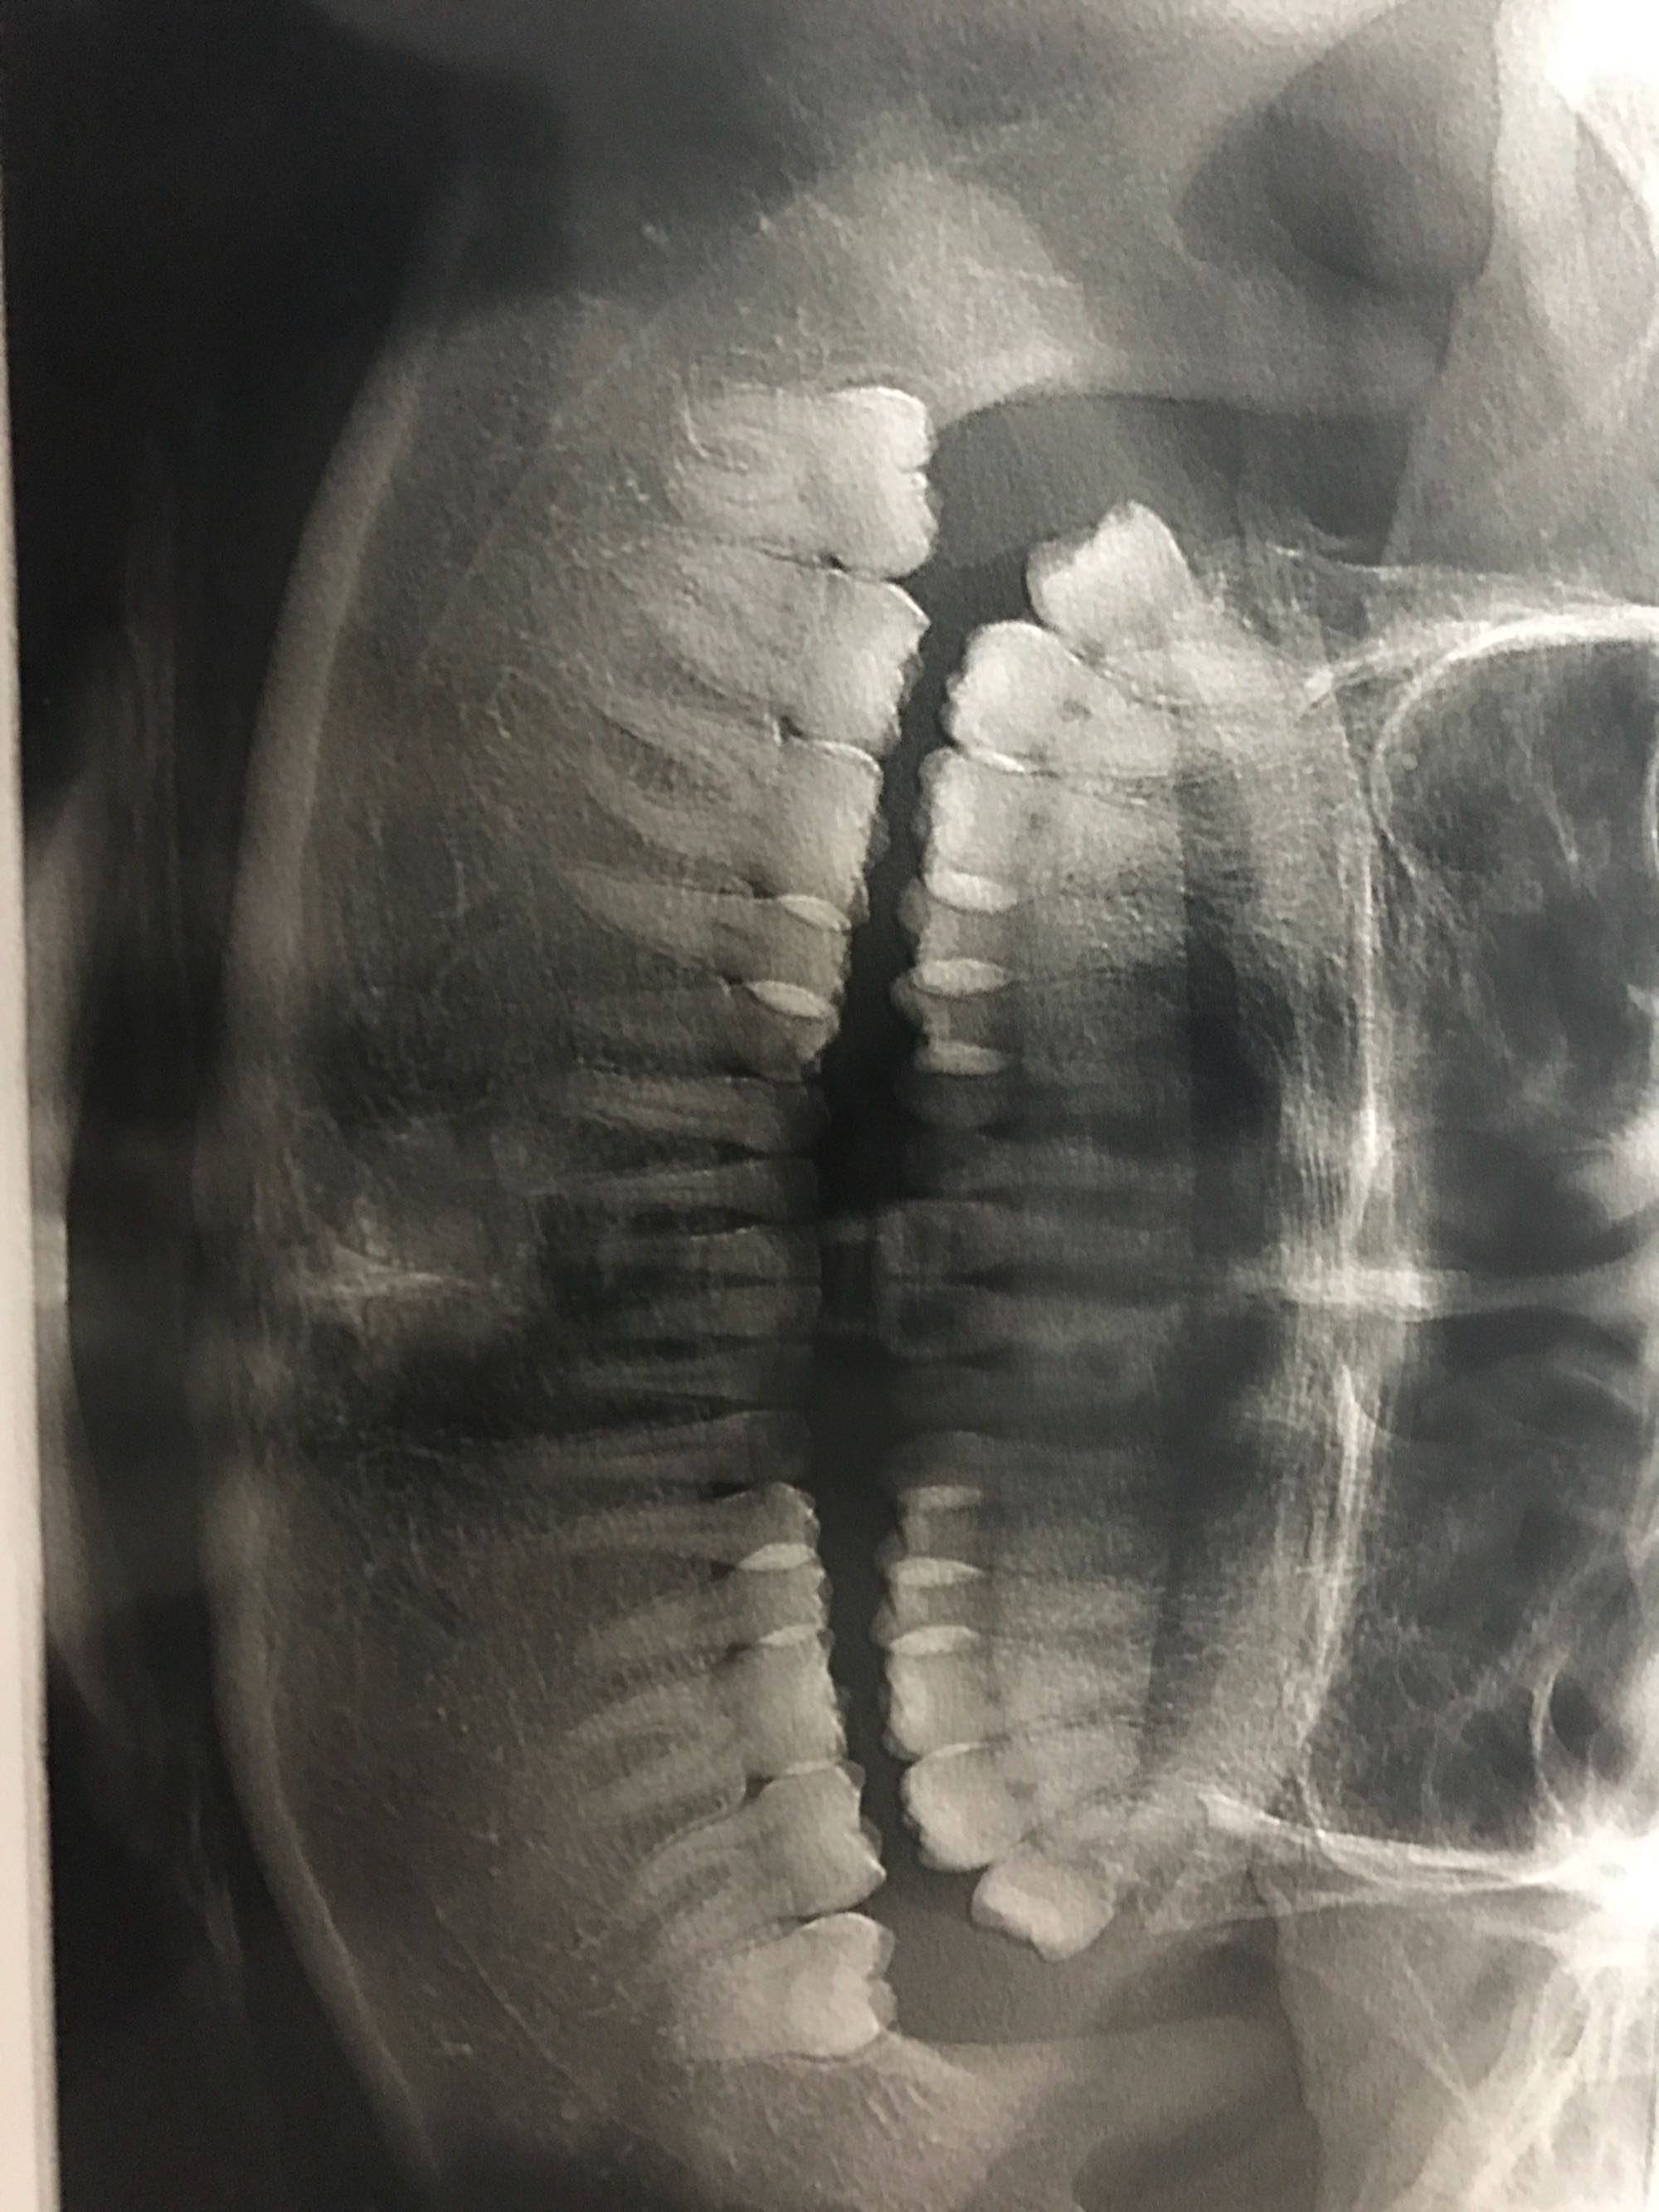

这样的智齿需要拔吗?突然开始关心我的牙,去拍了牙片医生和我说上牙可以拔,下牙在骨头里长着,没影响可以不用拔,请问需要拔牙吗?